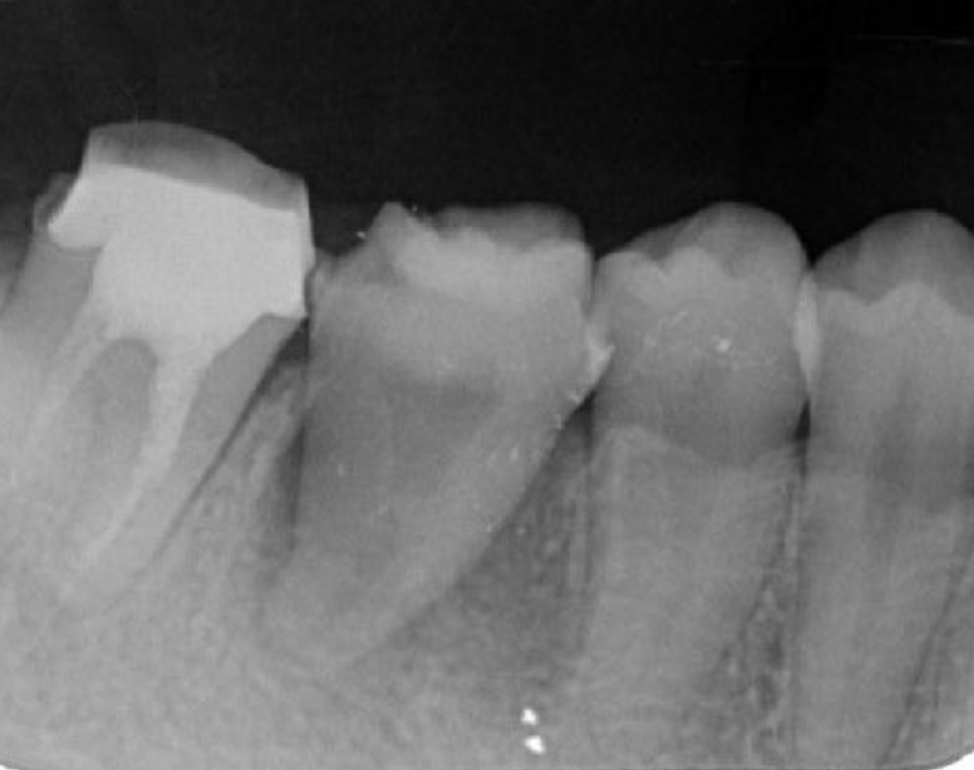

The patient requested auto transplantation in the lower left side jaw equivalent to #36, the tooth that was missing and replaced by a removable partial denture. The basic technique and procedure were the same as previously used for treatment of #48. Prior to the operation for #36, the buccal and proximal crown widths, and root length were measured using CBCT. In such cases, it is considered important to confirm the location of the inferior alveolar nerve, as well as the amount and depth of bone cutting needed by use of preoperative CT findings so as to prepare for treatment and ensure that the donor tooth can be placed smoothly in the socket (Figure 10). A trial application went smoothly, because the tooth was formed so as to be slightly larger than the root from the donor tooth (Figure 11, Figure 12).

Figure 11.Dental X-ray image obtained after autotransplantation from #38 to #36. The donor tooth root canal appeared to be blanched.

Following the operation, root canal treatment was performed as noted above. Functions including temporary crown occlusal contact and tooth mobility, as well as pocket depth were also checked. All examination results clearly indicated placement of a definitive prosthesis in the patient (Figure 13, Figure 14). At a follow-up examination one year after surgery, progress in this case was determined to be good (Figure 15).

Figure 13.Dental X-ray image obtained after confirmation of definitive prosthesis. Bone regeneration can be seen around the root of the donor tooth.

The transplantation process begins with a surgical procedure according to the following requirements; the recipient site should be prepared according to the donor tooth shape, time needed for recipient site preparation should be minimized, the number of fitting attempts using the donor tooth should be as few as possible, and extraction of the donor tooth should be gently performed. For realization of an ideal surgical setting, panoramic X-ray and CBCT results (Fig. 1-9) are essential for preoperative diagnosis. In the present case, root completeness, Moorrees classification 18, and donor tooth size were determined based on those results, which allowed us to form an operation plan. Regarding root morphology, a single rather than a compound root is ideal and a single-root tooth that tapers toward the root apex is best, as the risk of damage to the periodontal ligament during extraction is reduced.